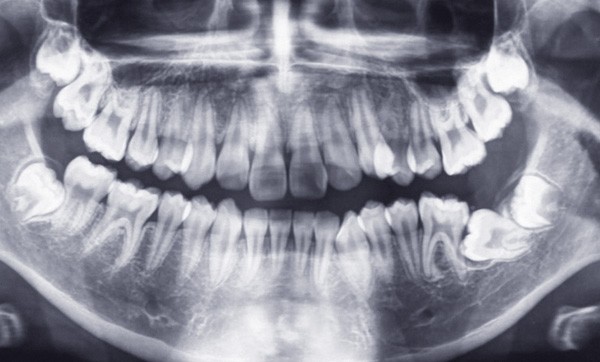

Sur le plan dentaire, au maxillaire, le patient présente une arcade en lyre avec de nombreuses malpositions (fig. 4). À la mandibule, la 37 est absente de l’arcade (fig. 5). Le patient présente une classe I d’Angle droite et gauche (fig. 6 et 7). Le surplomb et le recouvrement sont satisfaisants, les milieux sont alignés, et il existe une occlusion inversée 22/33 (fig. 8).

Le patient présente une DDM par encombrement antérieur et postérieur, des incisives mandibulaires vestibulo-versées et une 37 incluse en position horizontale (fig. 9).